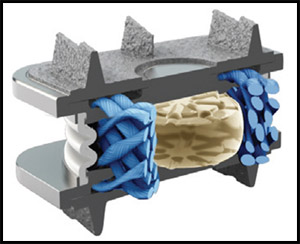

В настоящее время наиболее современным заменителем диска является искусственный диск. Наиболее близким по строению и функции к обычному диску является искусственный диск «М6-С». (Рис.5) Так же как и настоящий диск указанный имплант состоит 2-х частей: искусственного ядра, обеспечивающего осевое сжатие, и кольца из волокнистого материала, обеспечивающего подвижность с контролируемой амплитудой и с шестью степенями свободы. (Рис.6) Такая конструкция обеспечивает физиологическую подвижность позвоночно-двигательного сегмента и предотвращает дальнейшую дегенерацию дисков на уровне соседних позвонков. Биомеханические испытания искусственного диска М6-С подтвердили качество подвижности, эквивалентное человеческому диску.

| Рис.5. Искусственный диск М6-С. | Рис. 6. Устройство искусственного диска М6-С. |